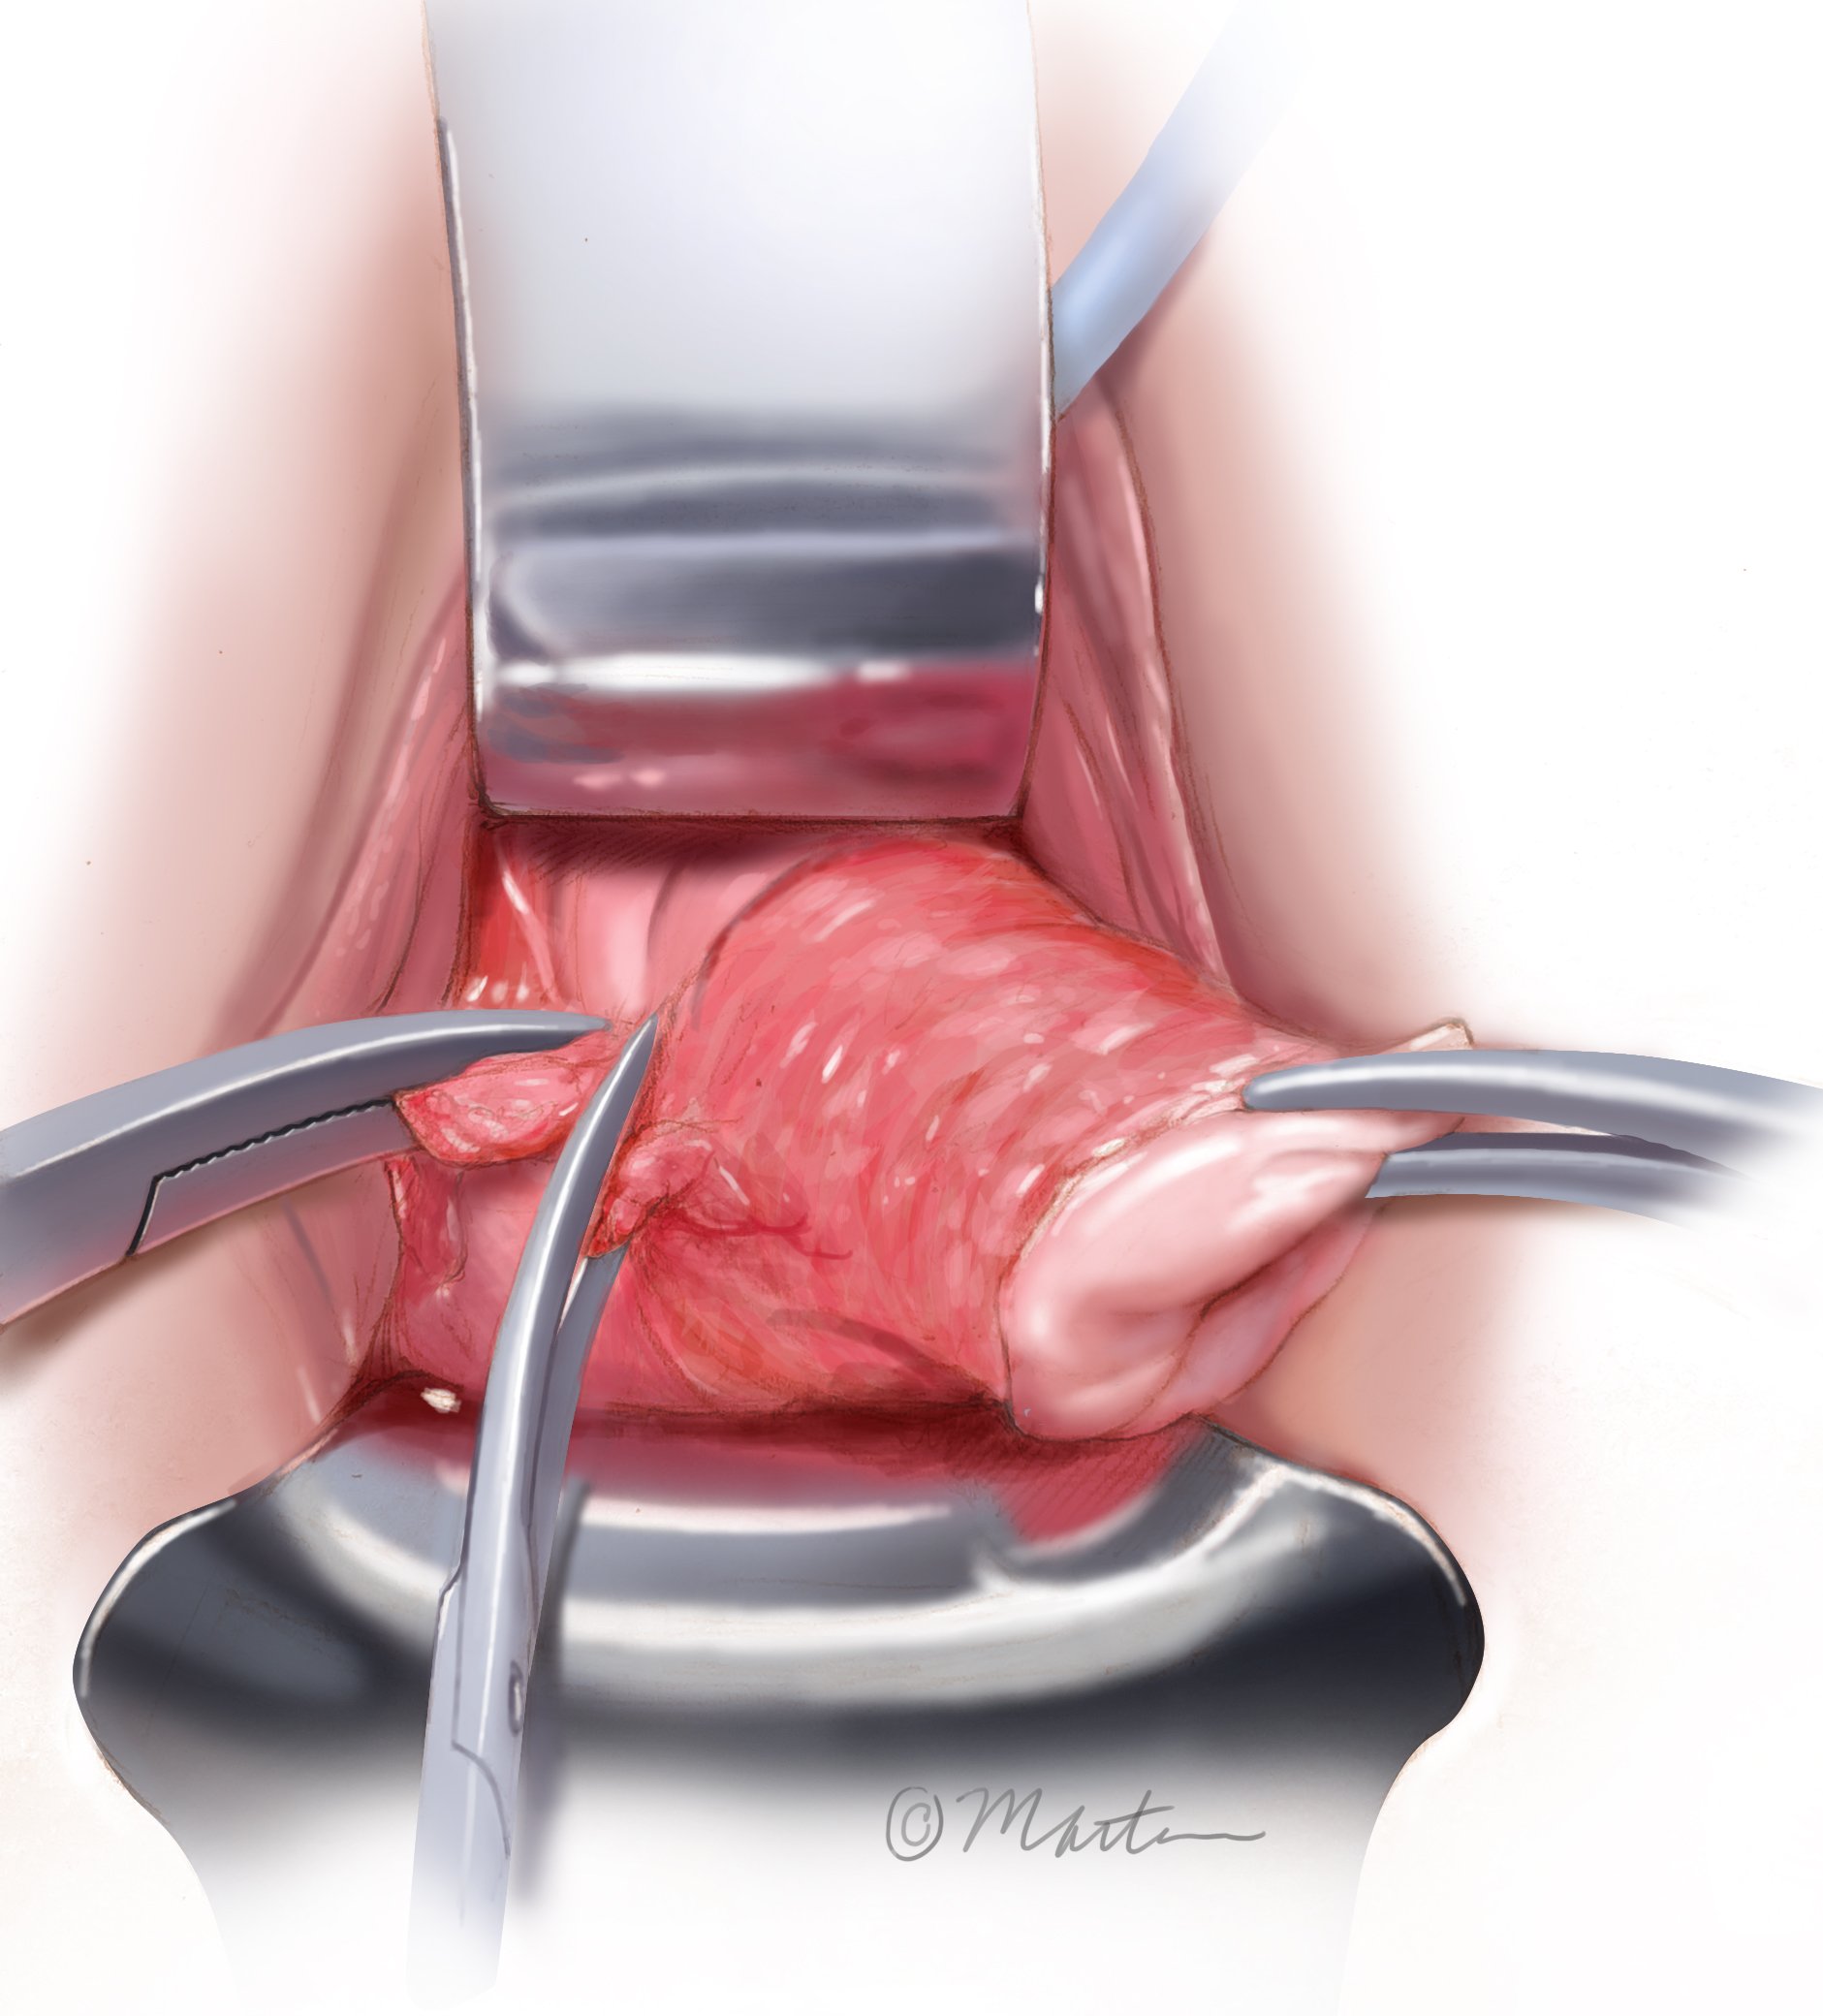

Total Vaginal Hysterectomy